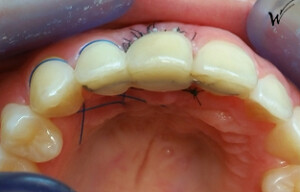

Cas clinique « SMILE RED FLAG MEI » : Traitement de remplacement d’une dent du sourire par un implant en Mise en Esthétique Immédiate. Visualisation de la version définitve de la couronne sur implant avec un cosmétique en céramique.

Après la guérison des tissus mous (gencive) et durs (os alvéolaire), la couronne céramique esthétique a été installée sur l’implant.

Le maintien de l’esthétique du sourire dépend en grande partie de la reconstruction des tissus gingivaux entourant la couronne céramique esthétique et de l’os autour de l’implant.

Cicatrisation des tissus et résultat clinique à la pose de la couronne céramique